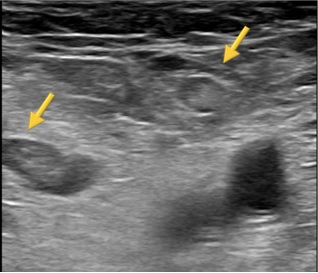

病例 53岁 女性;吞咽困难(weight loss) BMI 23 呼吸功能正常;胃镜发现胃腺癌,CT:T3NxM0 PET/CT:N0M0 MDT:新辅助化疗:FOLFOX4(x 4) 外科:Lewis-Santy pTNM:yT4N1M0 辅助 Chemo-radiation

Day 7: 胸膜渗出 (1.5L /day) +腹水 Ascites

胸导管穿刺